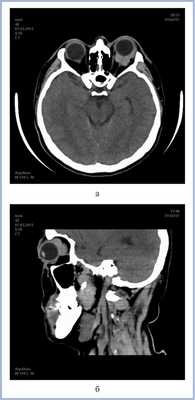

КТ позволила выявить ретробульбарную ткань с достаточно четкими границами, локализующуюся вокруг зрительного нерва, а также утолщение хориоидеи слева (рис. 4). Патологических изменений справа по данным КТ выявлено не было. С помощью УЗДС слева в В-режиме непосредственно за задним полюсом глаза (вокруг зрительного нерва) определяли гипоэхогенную, практически однородную опухолевую ткань с четкими неровными контурами. Одновременно выявили диффузное утолщение хориоидального слоя в области заднего полюса глаза — до 2,5 мм (рис. 5, а). Ультразвуковой денситометрический анализ, проведенный на основе двумерных серошкальных гистограмм, продемонстрировал крайне низкие значения акустической плотности ткани (А=3—12 усл. ед.) (см. рис. 5, б). В режиме цветового допплеровского картирования (ЦДК) отмечена гиперваскуляризация ретробульбарного и интраокулярных очагов с высокими линейными характеристиками кровотока. Следует отметить, что два указанных процесса — внутриглазной и орбитальный имели единую васкуляризацию (см. рис. 5, в). Патологических изменений в правом глазу по данным ультразвукового исследования выявлено не было.

Рис. 4. Компьютерная томограмма орбит в аксиальной (а) и сагиттальной (б) проекциях.

Рис. 5. Результаты дуплексного сканирования. а — утолщение хориоидеи; б — денситометрические показатели акустической плотности опухоли в В-режиме; в — множественные собственные сосуды опухоли, единая васкуляризация внутриглазного и орбитального очагов в режиме ЦДК.

Данные клинического и комплексного инструментального обследования позволили предположить лимфому с одномоментным вовлечением глаза и орбиты слева и начальный процесс с правой стороны.